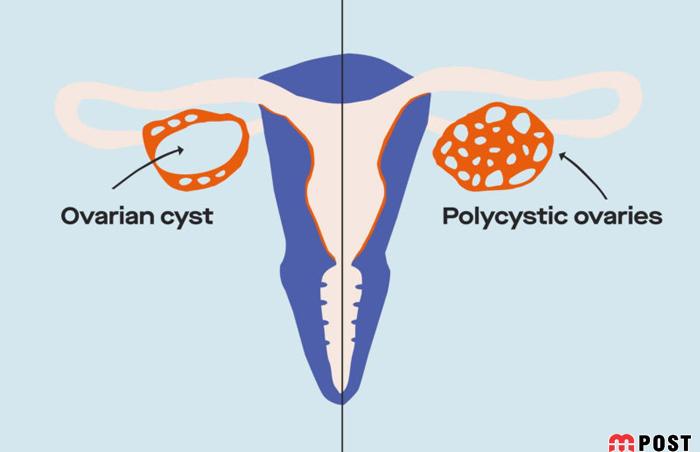

انواع مختلفی از کیستهای تخمدان وجود دارد که شایعترین آن کیست های فولیکولی است. این کیست ها در یکی از فولیکولهای تولیدکننده تخمک ایجاد میشود.

کیست های ساده (فولیکولی) با رشد قسمتی از تخمدان و تجمع مایع داخل آن مشخص میشوند، اندازه آنها معمولاً بالای ۳ سانتیمتر است و نباید با فولیکول تخمک که در زمان تخمکگذاری گاهی حتی به اندازه ۲۵ میلیمتر میرسد، اشتباه شوند.

نوع دیگری از کیست های تخمدان هستند که کسیت هموراژیک یا خونریزی دهنده نامیده می شوند. البته، این کیست ها بر خلاف اسمشان، معمولاً تأثیری بر باروری ندارند.